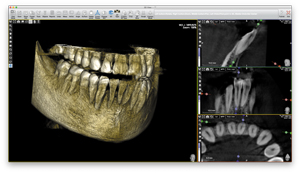

РАСШИРЕННАЯ ФУНКЦИОНАЛЬНОСТЬ ДЛЯ ИНТУИТИВНОЙ НАВИГАЦИИПрограммное обеспечение ACTEON Imaging Suite (AIS), совместимое с Windows и Mac, обеспечивает расширенную функциональность, интуитивно понятное управление изображениями и современные инструменты для упрощения планирования имплантации. Кроме того, настраиваемый отчёт улучшает общение с пациентом.

Программное обеспечение AIS позволяет управлять панорамными и КЛКТ-изображениями от получения до просмотра:

- Планирование имплантации

- Размещение короны

- Трассировка нижнечелюстного нерва

- Удобная навигация по разным разделам

- Измерение поверхности, расстояния и угла

- Существенная и масштабируемая библиотека имплантатов

- Распечатанный отчёт об имплантации

- Обмен информацией в сети

- Дела, экспортированные на компакт-диск или USB-накопитель

- Экспорт в формате STL

- Фильтр уменьшения металлических артефактов

- Панорамный и цефалометрический фильтр оптимизации деталей изображения

- ЛОР-модуль

- Виртуальный эндоскоп

- Интегрируется с различным программным обеспечением для управления пациентами

- DICOM-совместимый